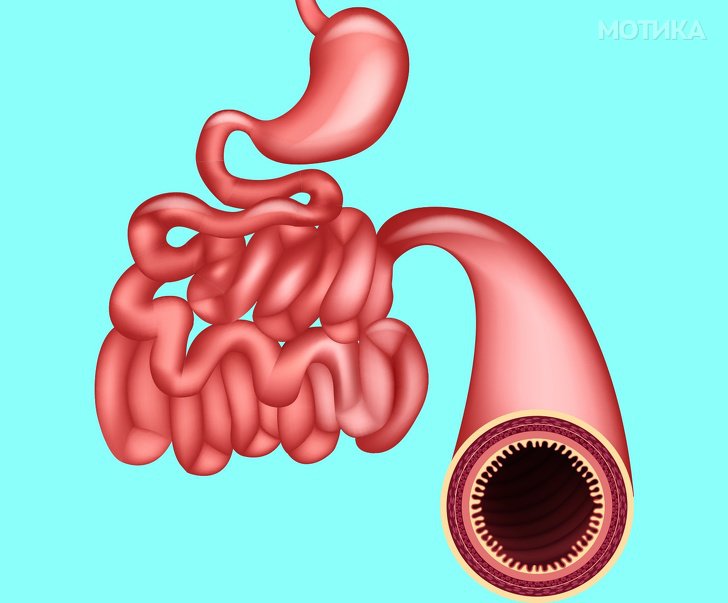

7. Тенко црево

- Тенкото црево го добило своето име поради неговата широчина, бидејќи всушност е најголемиот внатрешен орган во човечкото тело. Тенкото црево е долго околу 20 метри и доколку неговата површина се израмни, тоа ќе биде со големина од 2 тениски игралишта.

- Тоа содржи околу еден килограм бактерии.

- Интересно е тоа што во Јапонија имаат уникатна микроби во нивните црева кои помагаат да се процесира алгите побрзо.